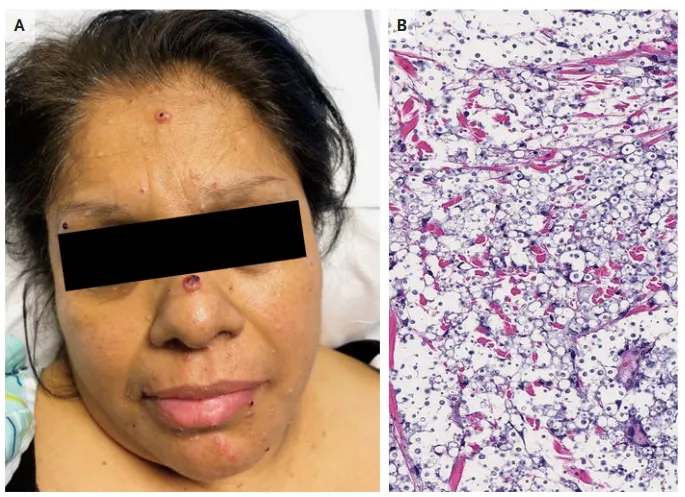

Uma causa incomum de hematúria glomerular intermitente!

Uma causa incomum de hematúria glomerular intermitente!

Hematúria pós infecção, caso clínicos para auxiliar no entendimento de causas glomerulares comuns e raras...